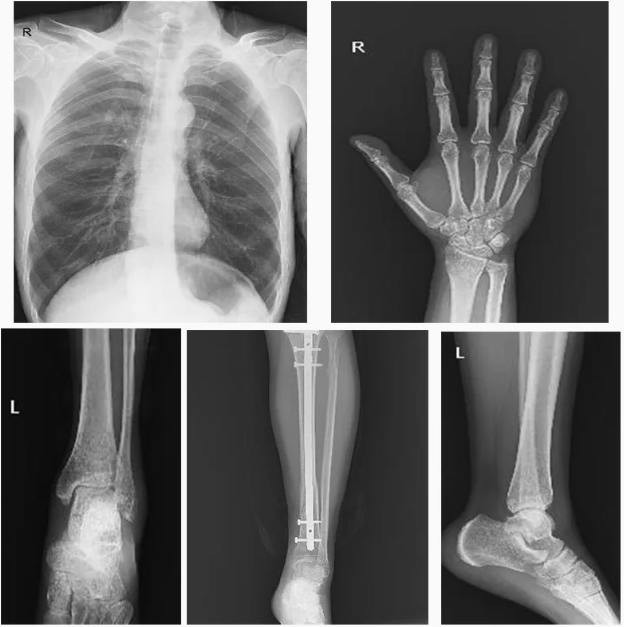

High Image Quality:

The My-D049R delivers high-resolution images with low radiation dose, which helps in obtaining accurate diagnostic results while minimizing the patient’s exposure to radiation.

Applications:

Hospitals:

Ideal for use in emergency departments, ICU, and surgery rooms where patients need immediate imaging.